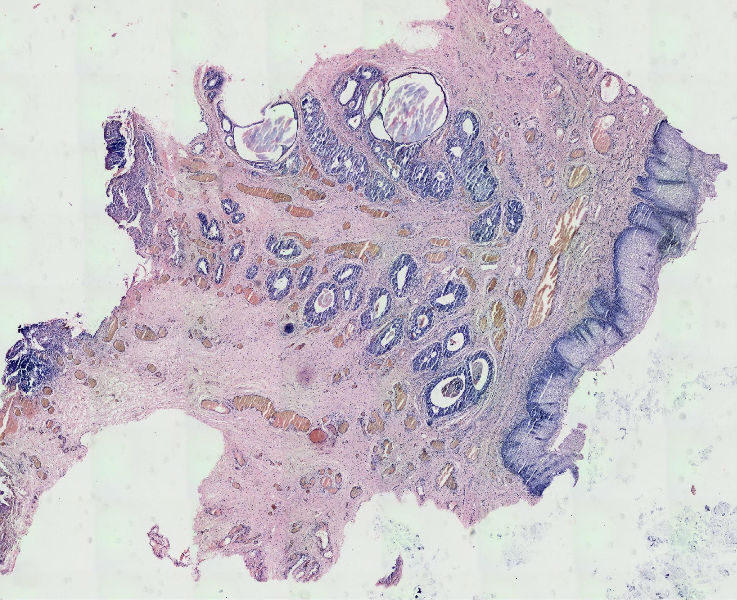

女57岁发现尿道外口息肉二周

图1

在传两个高倍